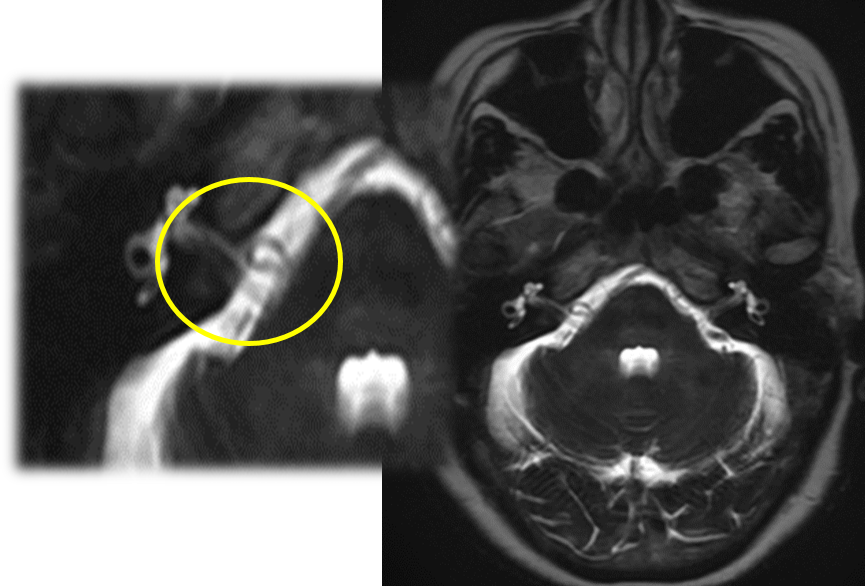

顔面神経は、脳幹から出たすぐのところで血管(前下小脳動脈など)と隣り合っています。加齢による動脈硬化などで血管が蛇行すると、この神経を圧迫しやすくなります。 血管の拍動が神経に伝わり、「異常な電気信号」が発生することで、顔がピクピクと動いてしまうのです。

顔面けいれんの確定診断と治療方針の決定には、MRI検査が極めて重要です。 当院では、3D-FIESTA(フィエスタ)やCISS(キス・シス)といった、神経と血管を非常に鮮明に映し出す特殊な撮像法を用いて、以下の情報を正確に把握します。

これらのMRI画像を3次元で再構成することで、神経と血管の位置関係を立体的な「設計図」として捉え、診断の精度を高めるだけでなく、安全な手術計画にも繋げています。

③ 手術療法(微小血管減圧術:MVD) 顔面痙攣を根本から治す唯一の治療法です。 耳の後ろの髪の生え際に約4cmの皮膚切開を行い、頭蓋骨に小さな穴を開けます。手術用顕微鏡を用いて、顔面神経を圧迫している血管を慎重に剥がし、テフロンというクッション材を間に挟むことで、再度の接触・圧迫を防ぎます。 経験豊富な脳神経外科専門医が執刀することで、合併症のリスクを最小限に抑え、非常に高い治癒率が期待できます。

主訴:数年前からの、”右まぶた”から”頬”にかけてのピクつき

”右まぶた”から”頬”にかけてのピクつきということでMRI検査を施行すると…